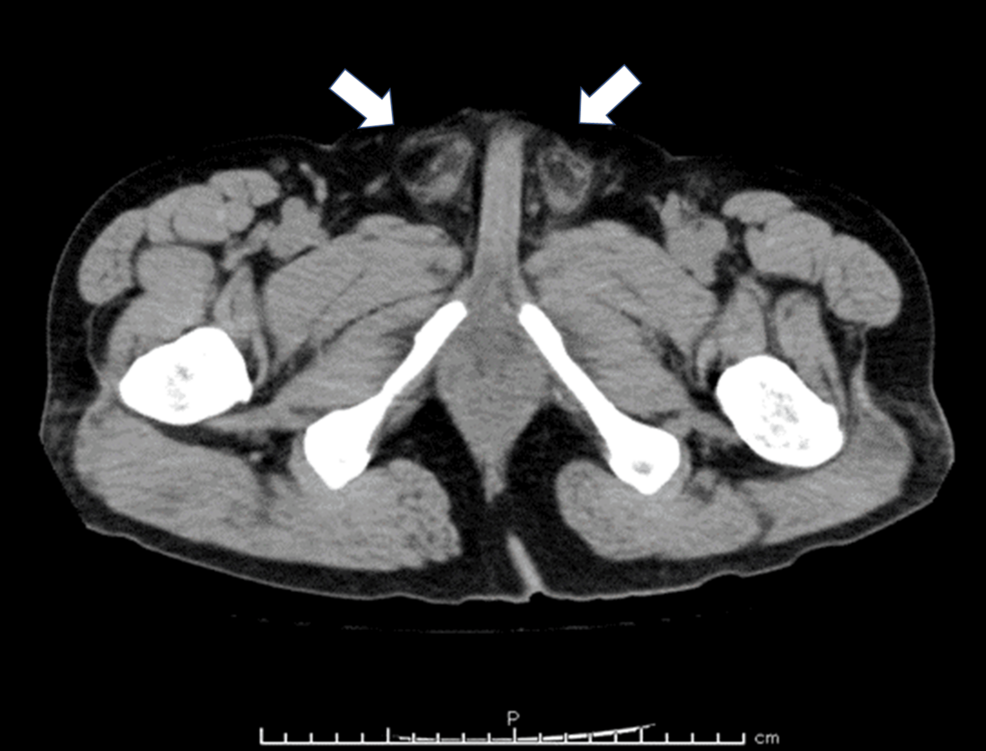

Figure 1: КТ органов малого таза, признаки острого орхоэпидидимита наблюдались в обоих яичках (белые стрелки).